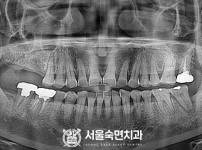

임플란트-전후사진1

치과를-선택할-때-꼭-확인하세요-서울숙면치과-임플란트-전후사진